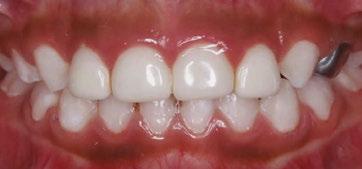

Case 3

A 4-year-old female presented with existing Silver Modified Atraumatic Restorative Technique (SMART) style restorations on #D, #E, #F, #G, and caries on other teeth. These anterior lesions

had been previously treated using SDF and covered with a HVGIC in a strip crown form. Though her lesions were stable from the clinical success of the SDF and HVGIC, these restorations were starting to fracture and demonstrate loss of material. The family wanted a more esthetic treatment option that would have a longer survivability. Additionally due to her high caries risk nature, a full coverage restoration with NuSmile® ZR anterior crowns were a more ideal solution in stabilizing her extensive decay pattern and covering staining from SDF therapy (Figure 4).

Figure 3: NuSmile® ZR Crowns were selected as a cementable full coverage restoration. At 6-month recall, apical tissues were healed with excellent gingival health Figure 4: SMART style restorations that were definitively restored with NuSmile® ZR Crowns as an esthetic option to cover SDF staining